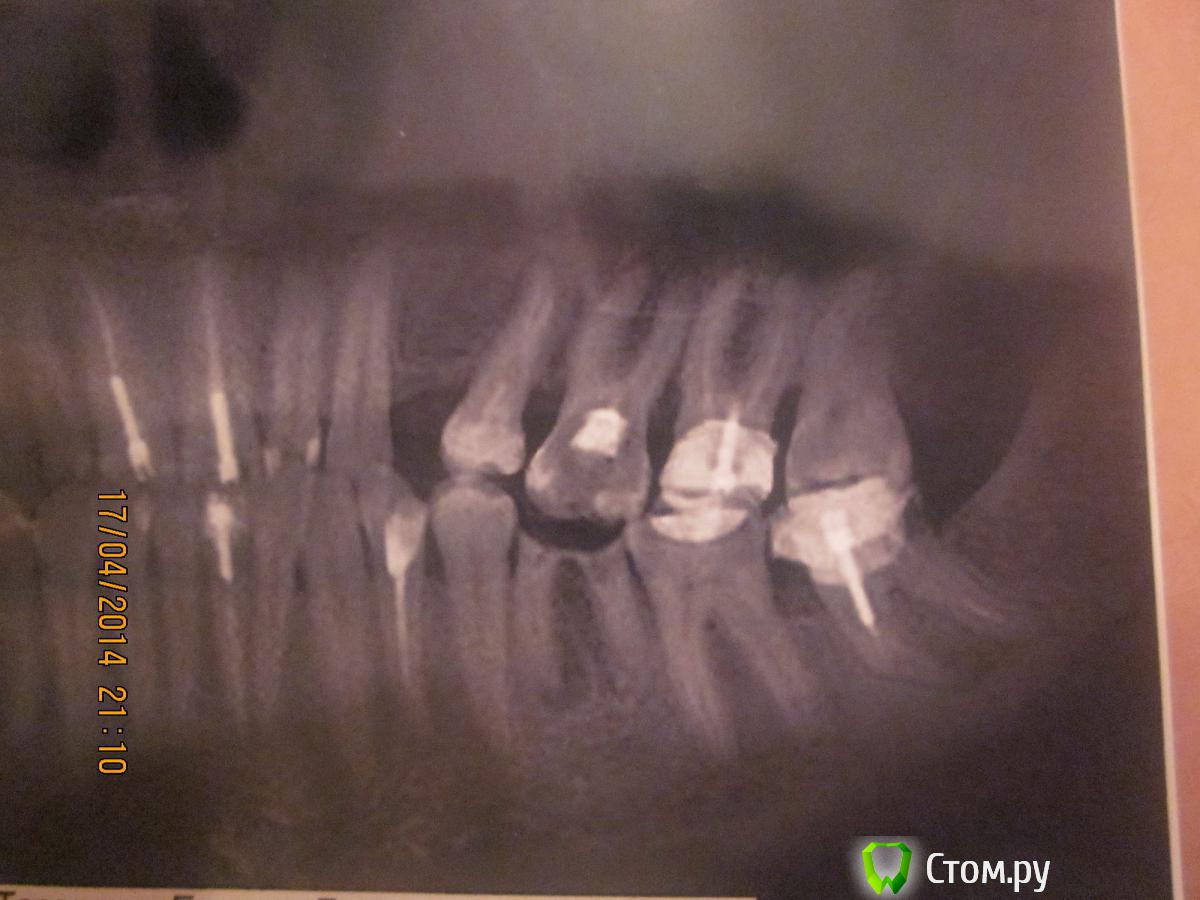

Евгения179 Опубликовано 17 апреля, 2014 Поделиться Опубликовано 17 апреля, 2014 Добрый вечер! У меня такой вопрос: неделю назад стало немного беспокоить в области моих проблемных 6 и 8ки. Знаю, что они на удаление, но пока не беспокоили, все откладывала. А тут дали о себе знать (только не знаю какой именно), при чем, почти нет болевых ощущений, иногда что-то где-то стрельнет, поноет и опять тишина. 1-Можно ли удалить сразу два?2-и если нет, то лучше сначала с какого начать? т.к. 6ка меня никогда не беспокоила, а на 8ку потратила зря деньги- оказалось после установки штифта, изменения на верхушке,но это выяснилось после лечения. И еще, на все у меня месяц, т.к уезжаю в отпуск.3-Реально ли без осложнений "расправиться " с двумя втечение месяца?Спасибо заранее! Ссылка на комментарий

Евгения179 Опубликовано 17 апреля, 2014 Автор Поделиться Опубликовано 17 апреля, 2014 Удаляйте сразу оба под одной анестезией и не медлите, с удалением проблем не должно быть, через неделю и не вспомните про них.Спасибо! Только у 6ки киста, так ли это? Значит с разрезом десны, накладки костной ткани? Ссылка на комментарий

CRAZYDUCK Опубликовано 17 апреля, 2014 Поделиться Опубликовано 17 апреля, 2014 (изменено) На верхнем 6 тоже проблема - прицельный надо сделать , кажется на небном корне есть расширение небольшое , но нужно снимок верхнего 6 ,может он стреляет ? Он у Вас опустился в сторону нижнего 6 сильно , думаю его по- возможности перед отпуском тоже пролечить ( ну или начать его лечение ).почему Вы не протезируетесь после удаления , у Вас на верхней челюсти сильно изменилось положение зубов , нижний 6 удалите и верхний 6 может еще больше опуститься , сложнее будет врачу потом хорошо и качественно сделать протез( имеется в виду любую конструкцию , которую Вы выберете), . Но это риторический вопрос , думаю Вам об этом говорили уже , а как и у всех - дела , заботы и год пролетел . Не откладывайте надолго протезирование. Изменено 17 апреля, 2014 пользователем CRAZYDUCK 1 Ссылка на комментарий